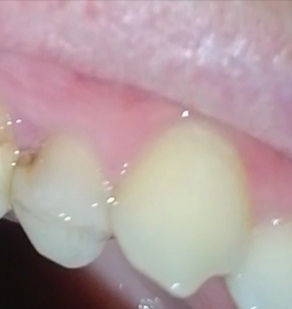

Аноним 10/08/25 Вск 18:26:58 1635518 35

1000070960.jpg 313Кб, 1117x832

1117x832

1000070961.jpg 180Кб, 882x704

882x704